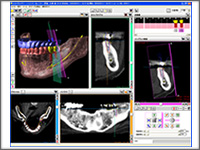

iCATシステムとは

CT撮影によって得られた患者様の口腔データよりコンピュータ上でインプラント埋入のシミュレーションを 行います。シミュレーションの結果を基に実際のインプラント手術を行う前に、患者様へ充分な治療計画のご説明を行い、安全で確実なインプラント手術を行います。 CT撮影によって得られた患者様の口腔データよりコンピュータ上でインプラント埋入のシミュレーションを 行います。シミュレーションの結果を基に実際のインプラント手術を行う前に、患者様へ充分な治療計画のご説明を行い、安全で確実なインプラント手術を行います。